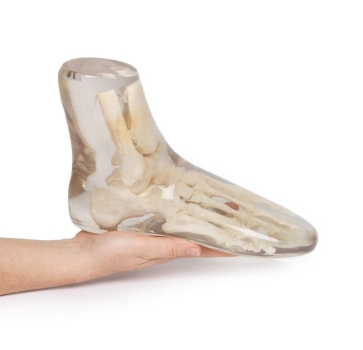

Dieses Röntgen-Teilphantom bietet Ihnen die einmalige Möglichkeit, reale Röntgenaufnahmen so oft Sie wollen zu wiederholen. Das Modell enthält echte menschliche Knochen und erlaubt so, echte Aufnahmen zu machen. Das Modell eignet sich perfekt für Schulen und Ausbildungsstätten, aber natürlich auch für die Medizintechnik, da verschiedene Einstellungen mit dem gleichen Körperteil wieder und wieder ausprobiert werden kann, ohne dass eine Gefährdung des Patienten in Kauf genommen werden muss. Das Modell ist in transparentem Kunststoff fest eingebettet. Diese Ausführung ist mit einem undurchsichtigen Lack versehen, so dass die inneren Strukturen nicht zu erkennen sind. Bei diesem Modell handelt es sich um ein handgefertigtes Einzelstück, das in seiner Größe und Ausführung abweichen kann. Bedingt durch das Fertigungsverfahren können im Innern des Phantoms Verfärbungen oder Risse vorhanden sein, dies ist produktionsbedingt und stellt keinen Defekt dar. Der Verkauf dieses Modells erfolgt nur gegen Nachweis der medizinischen Verwendung.

Fußskelett mit Unterschenkelansatz.